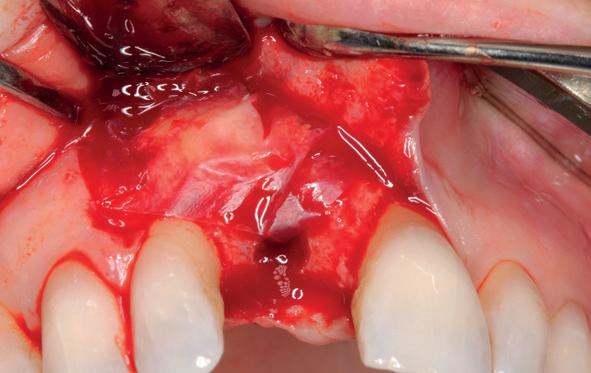

Lateraal van de implantaten wordt de kaak fors uitgebouwd volgens de Hybride GBR-techniek met Oragraft (allograft) van Lifenet die wordt vermengd tot een cocktail met BioOss (xenograft) van Geistlich, autoloog geoogste botsnippers en verzameld bloed uit het wondgebied. De botgraft wordt bedekt met een Ossix (crossed linked) membraan en met Hyadent (hyaluronzuur) overspoten. De sinuslift wordt gelijktijdig met de laterale botopbouw volgens de Caldwell Luc methode uitgevoerd en de uitgeprepareerde holte opgevuld met de botgraft. De flaps worden eerst horizontaal ontlast (gemobiliseerd) en vervolgens naar elkaar toe gehecht met vicryl rapide. Daarbij wordt gebruikgemaakt van horizontale matrassen, zodat de wondranden passief tegen elkaar

komen te liggen en de flaps primair gesloten kunnen worden. Het passief sluiten van een flap voorkomt wonddehiscenties in de genezingsfase die als complicaties kunnen optreden en botregeneratie verstoren. Daarnaast wordt bij een wonddehiscentie het risico op infectie van de graft sterk verhoogd waardoor het gewenste resultaat niet kan worden bereikt. Afstoting van graft materiaal komt dan veelvuldig voor soms gecombineerd met abcesvorming als geen voorzorgsmaatregelen worden genomen. Complicaties moeten daarom nauwlettend gevolgd worden totdat ze verdwenen zijn. De patiënt krijgt na chirurgie postoperatieve instructies en adviezen over de postoperatieve zorg. Daarbij wordt ook de nadruk gelegd op het koelen (coldpack) en zijdelingse druk op de wang. Het blijkt dat koelen en het uitoefenen van druk op het operatiegebied oedeem en hematoomvorming grotendeels kunnen verminderen en soms zelfs kunnen voorkomen.